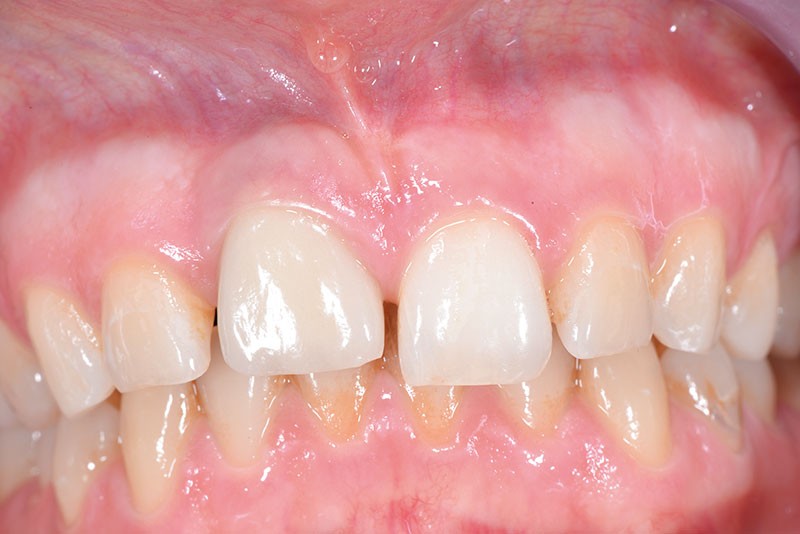

Une patiente âgée de 28 ans consulte pour un problème esthétique au niveau de la dent 11, porteuse d’une couronne implanto-portée (fig. 1a).

L’examen clinique révèle une différence d’alignement et un tissu gingival péri-implantaire peu épais sur cette couronne implanto-portée.